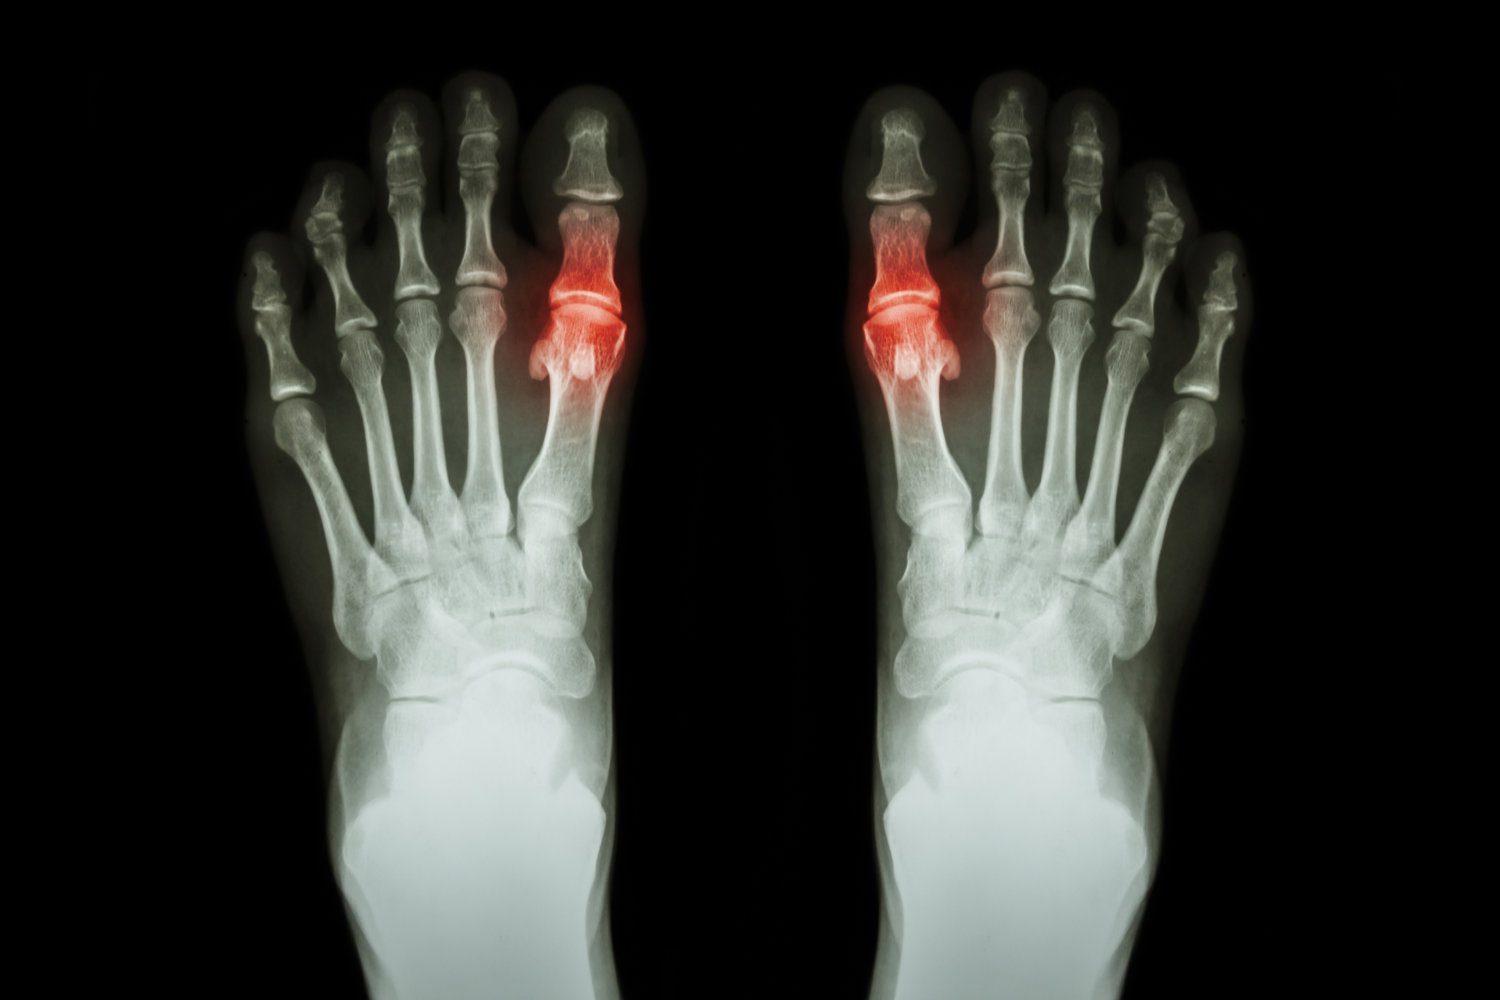

Gout

Gout is a form of arthritis that occurs as a result of the build-up of uric acid in ...